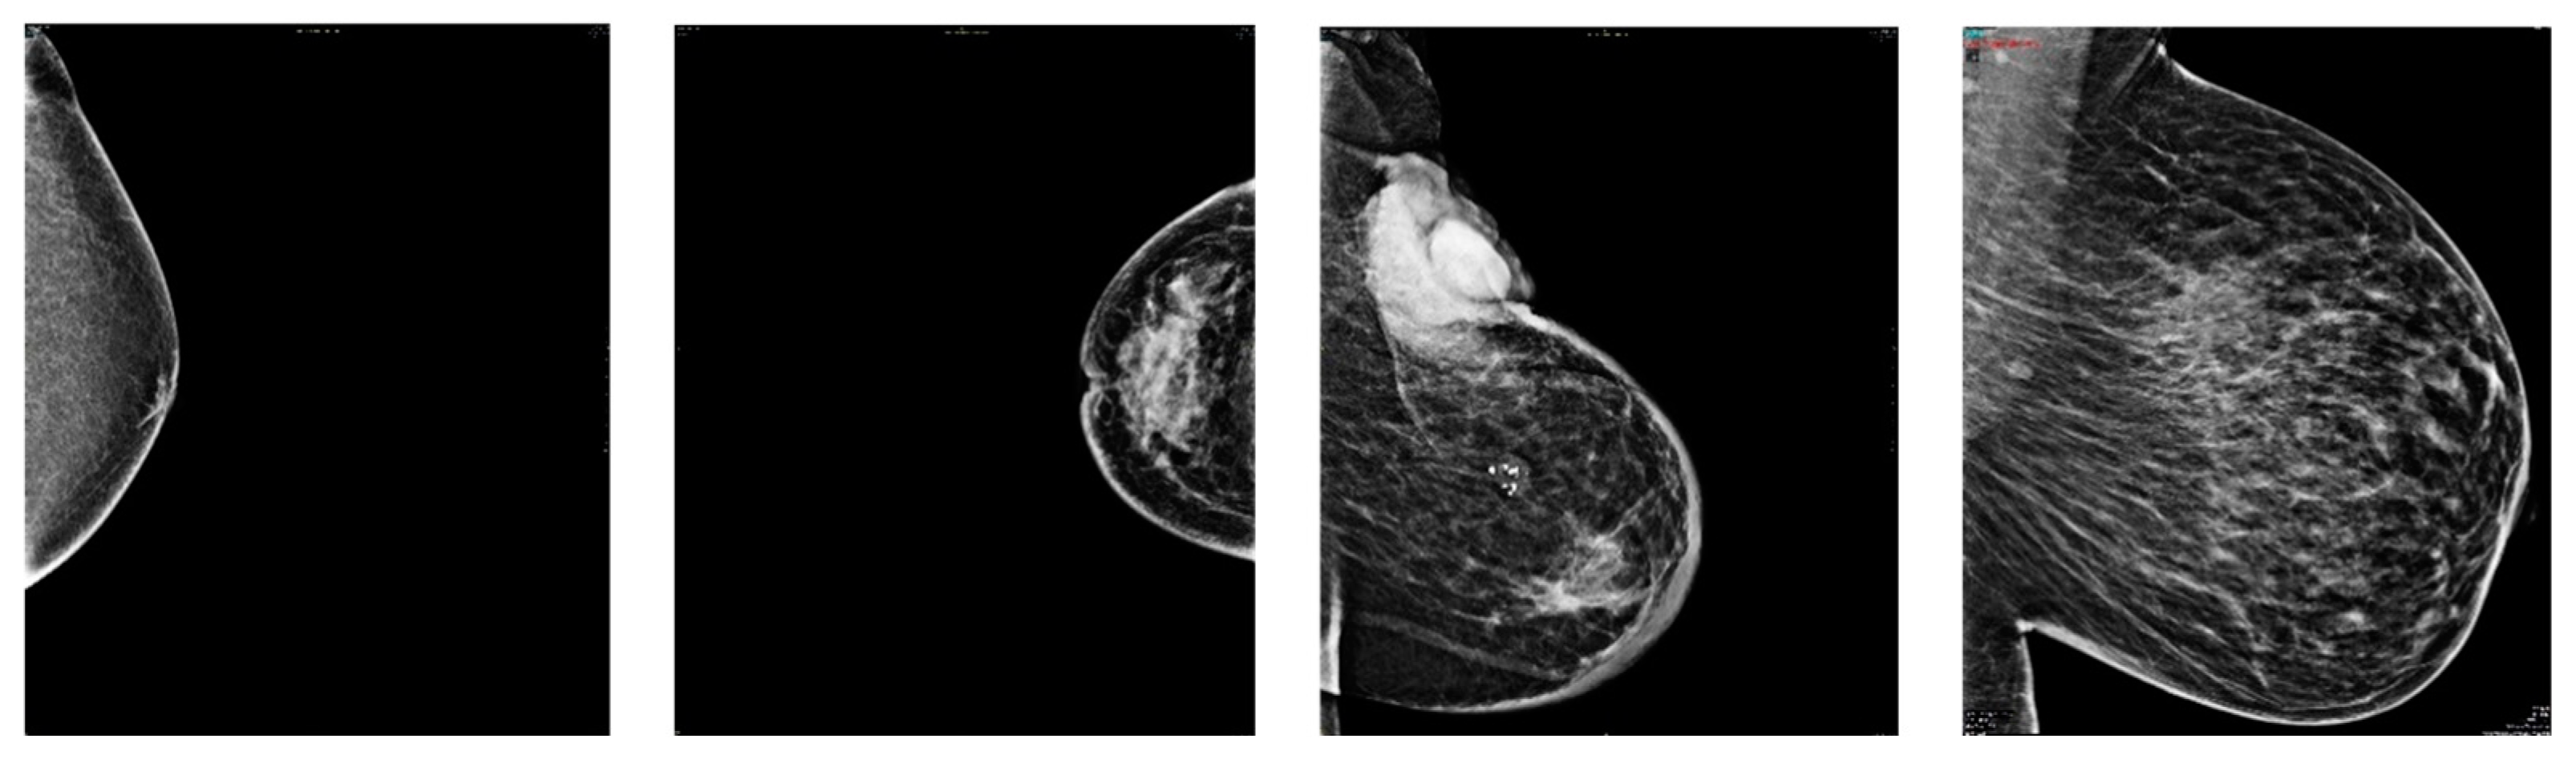

3.1. Dataset Descriptions

3.2. Mammogram Classification Using Deep Learning

3.3. Preprocessing